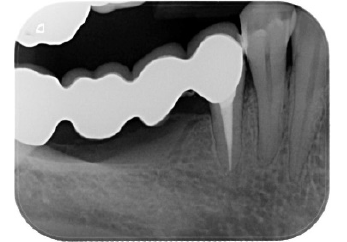

very natural and bio-mimetic emergence profile. At last (Figure

13-16) the radiographic history of the case, with the edentulous

ridge and the old long span bridge, the implants placed after ridge

augmentation, its relationship to the bone crest at the time of

impressions and four years after the final restoration was delivered.

Figure 13:Initial rx.

Figure 14:rx implants.

Figure 15:Impression.

Figure 16:Final restoration (4y).